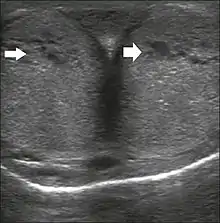

Ultrasonography

Penile ultrasonography with doppler can be used to examine the erect penis. Most cases of ED of organic causes are related to changes in blood flow in the corpora cavernosa, represented by occlusive artery disease (in which less blood is allowed to enter the penis), most often of atherosclerotic origin, or due to failure of the veno-occlusive mechanism (in which too much blood circulates back out of the penis). Before the Doppler sonogram, the penis should be examined in B mode, in order to identify possible tumors, fibrotic plaques, calcifications, or hematomas, and to evaluate the appearance of the cavernous arteries, which can be tortuous or atheromatous.[22]

Erection can be induced by injecting 10–20 µg of prostaglandin E1, with evaluations of the arterial flow every five minutes for 25–30 min (see image). The use of prostaglandin E1 is contraindicated in patients with predisposition to priapism (e.g., those with sickle cell anemia), anatomical deformity of the penis, or penile implants. Phentolamine (2 mg) is often added. Visual and tactile stimulation produces better results. Some authors recommend the use of sildenafil by mouth to replace the injectable drugs in cases of contraindications, although the efficacy of such medication is controversial.[22]

Before the injection of the chosen drug, the flow pattern is monophasic, with low systolic velocities and an absence of diastolic flow. After injection, systolic and diastolic peak velocities should increase, decreasing progressively with vein occlusion and becoming negative when the penis becomes rigid (see image below). The reference values vary across studies, ranging from > 25 cm/s to > 35 cm/s. Values above 35 cm/s indicate the absence of arterial disease, values below 25 cm/s indicate arterial insufficiency, and values of 25–35 cm/s are indeterminate because they are less specific (see image below). The data obtained should be correlated with the degree of erection observed. If the peak systolic velocities are normal, the final diastolic velocities should be evaluated, those above 5 cm/s being associated with venogenic ED.[22]